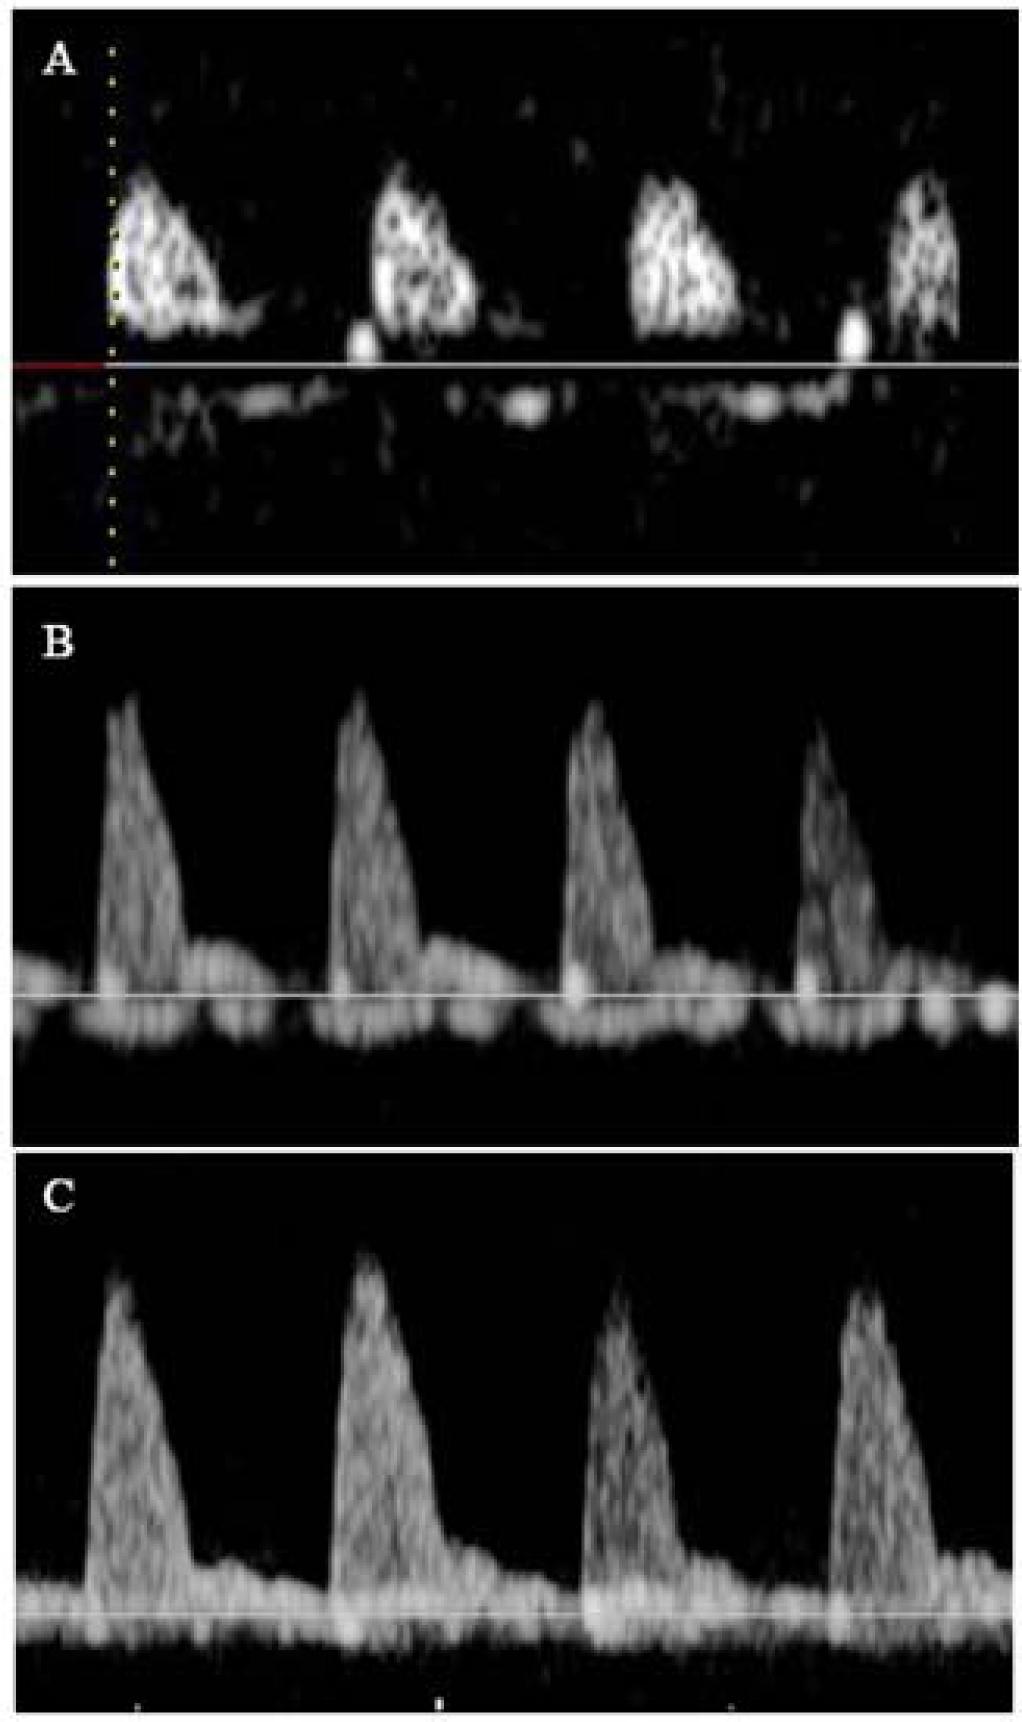

Figure 1

Figure 2

Figure 3